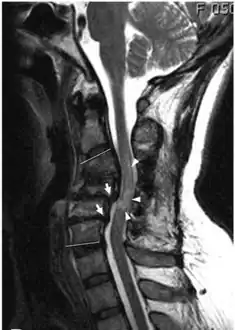

MRI shows retrolisthesis arrows ( and signal change at C3-C5 arrow heads)